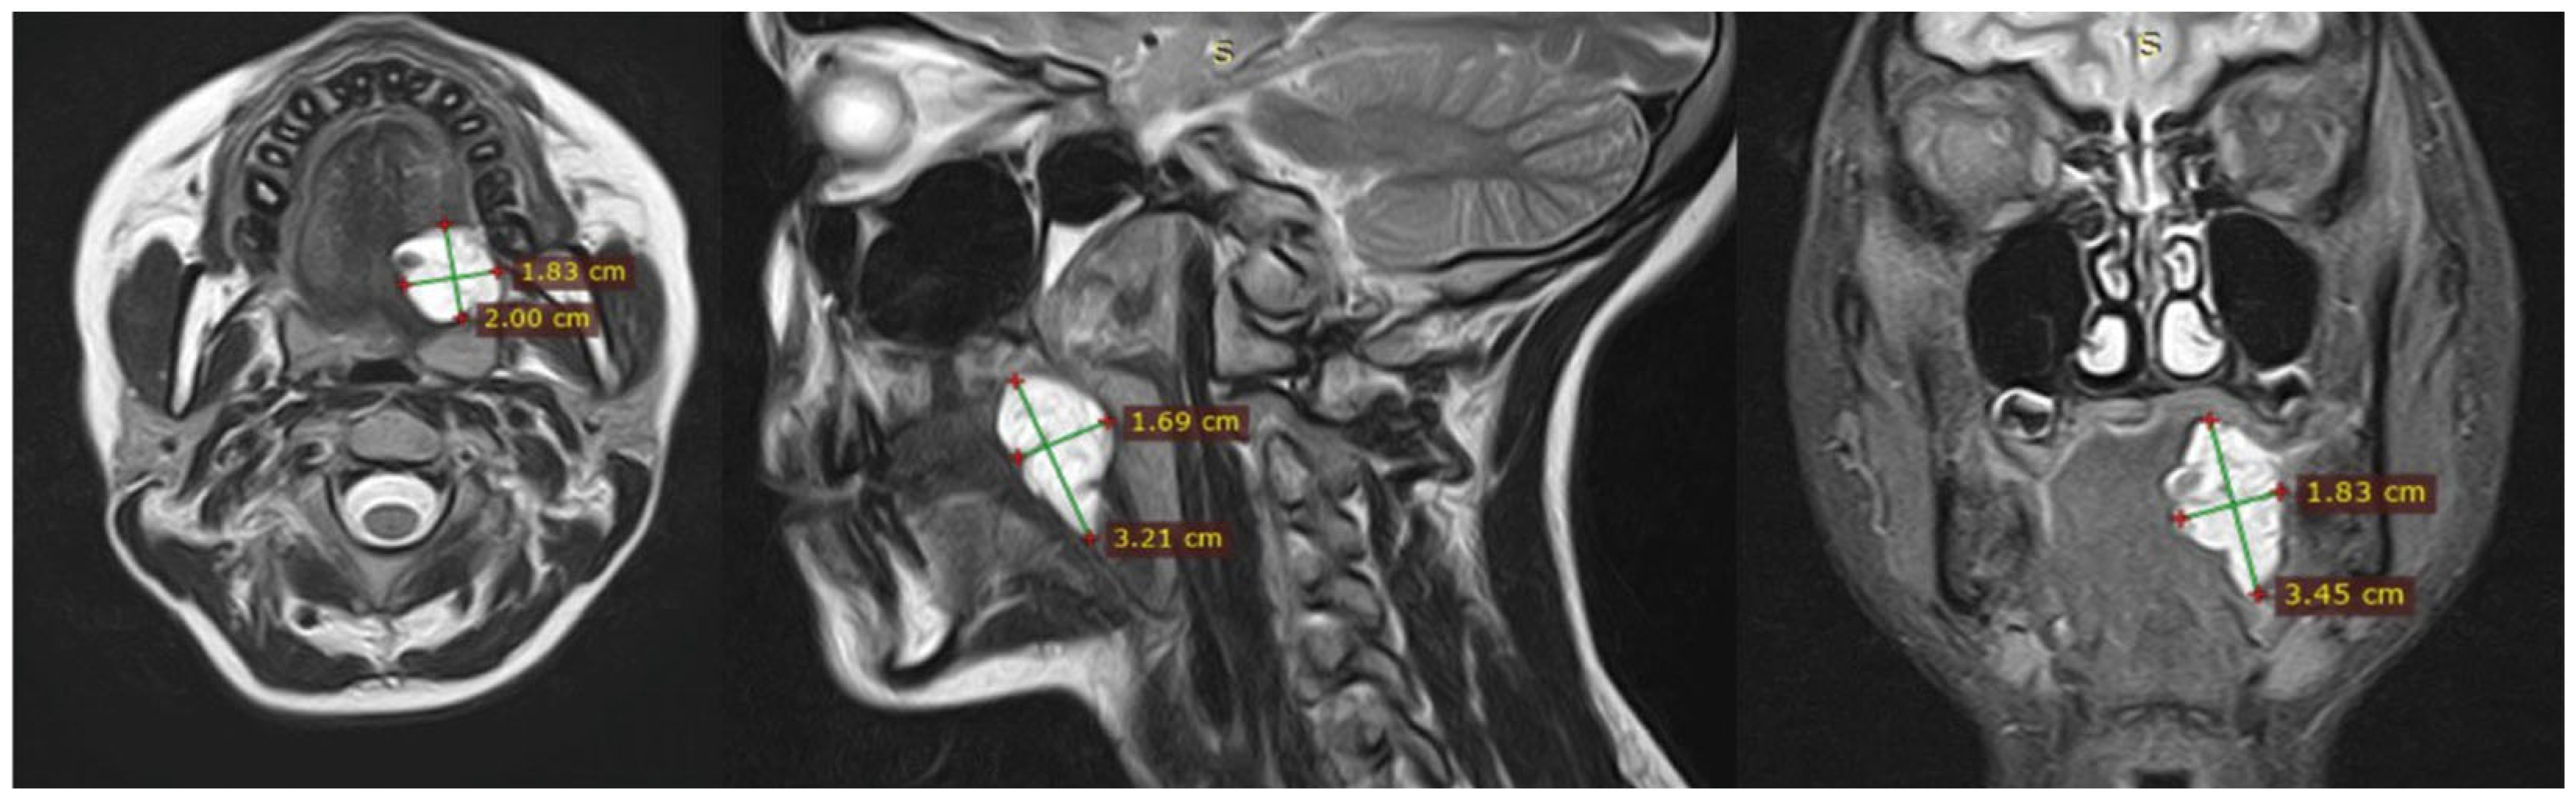

3.1. Magnetic Resonance Imaging (MRI) Findings

| No. | Sex | Age | Lesion Location | No. of Sessions | Volume Before (mm3) | Volume After (mm3) | Treatment Outcomes | Complications |

|---|---|---|---|---|---|---|---|---|

| 1 | F | 14 | Right tongue root, right floor of mouth | 1 | 6853 | 0 | Complete response (after 1st session) | None |

| 2 | M | 12 | Right tongue root | 2 | 6417 | 0 | Complete response | None |

| 3 | F | 13 | Left tongue root | 1 | 5129 | 0 | Complete response (after 1st session) | None |

| 4 | F | 37 | Oropharynx, posterior wall | 2 | 6938 | 0 | Complete response | None |

| 5 | M | 4 | Right soft palate | 1 | 3287 | 0 | Complete response (after 1st session) | None |

| 6 | F | 47 | Right soft palate | 1 | 2954 | 0 | Complete response (after 1st session) | Yes (painful necrosis) |

| 7 | F | 26 | Soft palate and uvula | 1 | 6711 | 0 | Complete response (after 1st session) | Yes (subclinical necrosis) |

| 8 | M | 4 | Right soft palate | 1 | 4386 | 0 | Complete response (after 1st session) | None |

| 9 | M | 9 | Oropharynx | 6 | 7334 | 3091 | Significant reduction (>50%) | None |

| 10 | M | 23 | Subglottic space, neck | 3 | 8217 | 3248 | Significant reduction (>50%) | None |

| 11 | M | 56 | Tongue and floor of mouth | 3 | 9476 | 3815 | Significant reduction (>50%) | None |

| 12 | F | 14 | Total tongue involvement | 12 | 10,192 | 4090 | Significant reduction (>50%) | None |

| 13 | F | 67 | Soft palate and uvula | 3 | 8743 | 5668 | Limited reduction (<50%) | Yes (subclinical necrosis) |

| 14 | M | 5 | Right soft palate and palatopharyngeal arch | 3 | 9159 | 5340 | Limited reduction (<50%) | None |